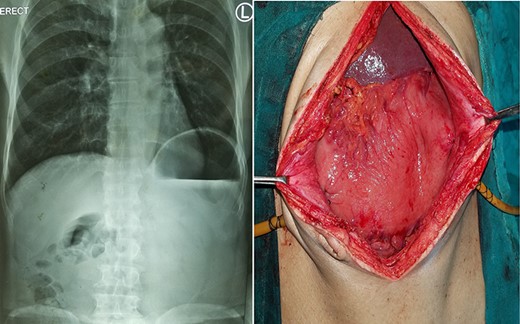

A 75-year-old male presented to the emergency with severe pain in the epigastrium, multiple episodes of non-bilious vomiting and epigastric fullness for the past 2 days. There was no history of weight loss, anorexia, hematemesis or early satiety. Eight months before, he had similar complain (resolved spontaneously), was admitted, and evaluated with upper GI endoscopy and CT abdomen, with normal findings. On examination, patient was tachycardic but normal blood pressure. There was epigastric fullness with mild tenderness. Blood investigations revealed normal hemoglobin, but leukocytosis (16 000 cells/mm3). The renal function test and serum chemistry were normal. Chest X-ray was done, which showed elevated left hemi-diaphragm with large gastric shadow beneath it (Fig. 3). In view of recurring symptoms, chronic gastric volvulus was considered as differentials. On further imaging with CT abdomen, it confirmed gastric volvulus. Patient was taken up for emergency laparotomy. Intraoperatively, organo-axial gastric volvulus secondary to diaphragmatic eventration was seen. It was de-rotated and fixation of the stomach was performed by double, non-draining tube gastrostomy (at two points, body and antrum) with sham gastrojejunostomy to prevent recurrence (Fig. 3). No attempt at the plication of eventration was done due to the technical difficulty, splenic capsular tear and secured stomach fixation. The patient did well postoperatively and was discharged on Day 8. At 38 months follow-up, the patient is asymptomatic.

Chronic gastric volvulus, showing raised left hemi-diaphragm in chest X-ray, with intraoperative placement of double gastrostomy tube for fixation.